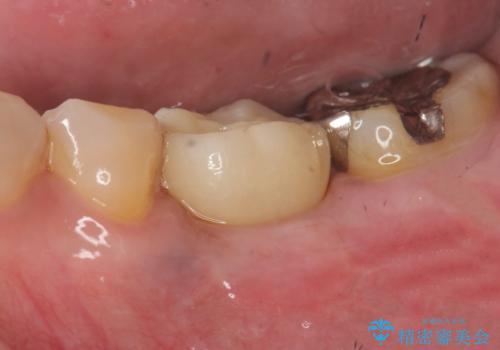

[ 2歯連続欠損 ] インプラントによる機能回復

![[ 2歯連続欠損 ] インプラントによる機能回復 の症例 治療後](https://seimitsushinbi.jp/wp/wp-content/uploads/2021/06/e9f570392fb27dc25eb48513f3cfe24e-500x350.jpg?v=1623390671)